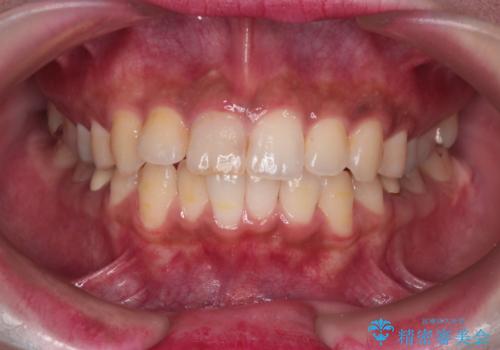

前歯の突出感を改善|上下4本の抜歯と審美ワイヤー矯正でバランスの取れた口元へ

- 患者様は、前歯の突出感を気にされて来院されました。診察の結果、歯列のスペースが不足しており、前歯を後方へ移動させるには抜歯が必要と判断。上下の小臼歯4本を抜歯し、目立ちにくい審美ワイヤー矯正(白いワイヤーと透明ブラケット)を使用して治療を行う計画を立てました。

抜歯によって前歯を下げるためのスペースを確保。その後、審美ワイヤー矯正を用いて、歯列全体のバランスを整えながら前歯を後方へ移動させました。治療後は、横顔のラインが整い、自然な口元になったことで、見た目も噛み合わせも改善しました。患者様からは「口元がすっきりして、自信を持って笑えるようになった」と喜びの声をいただきました。